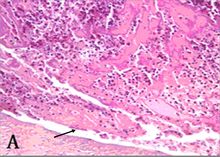

箭頭所指為鏡下的白色血栓肉眼:呈灰白色小結節或贅生物狀,

表面粗糙有波紋,質硬,與血管壁緊密黏著不易脫落。 鏡下: 由血小板及少量纖維蛋白構成,還有大量中性白細胞。